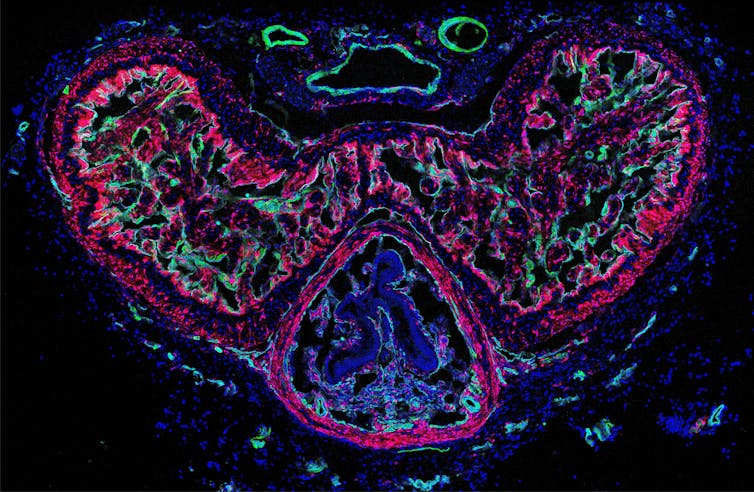

This penis “sponge” is scientifically termed corpora cavernosa. Erections depend on the influx and trapping of blood. Smooth muscle cells regulate the blood flow into the sponge and its subsequent firmness. In a recent study, my colleague and I delved into the role of penile fibroblasts, the most abundant cells in the human penis, about which little was previously known.

We discovered that penile fibroblasts help smooth muscle cells to relax. Using a technique to render cells light-sensitive enabled us to activate fibroblasts by shining blue light from outside onto the penises of mice.

We found that light-induced activation of fibroblasts relaxed smooth muscle cells and increased blood flow. The effectiveness of this relaxation-support depends on the number of fibroblasts. More fibroblasts led to easier relaxation and increased blood flow.